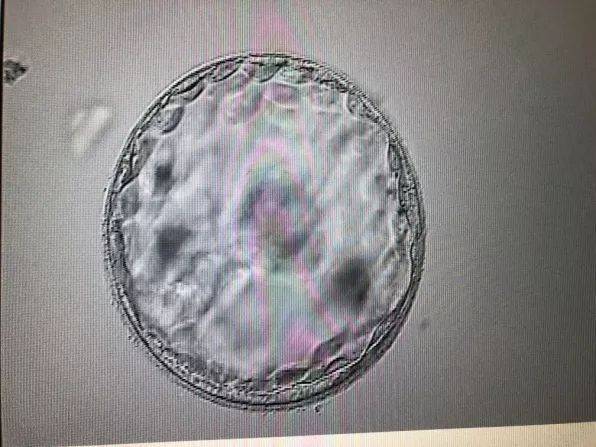

五个月胎儿生殖发育图片

以下为五个月胎儿生殖发育的图片,可以直观地了解胎儿生殖器官的发育情况。